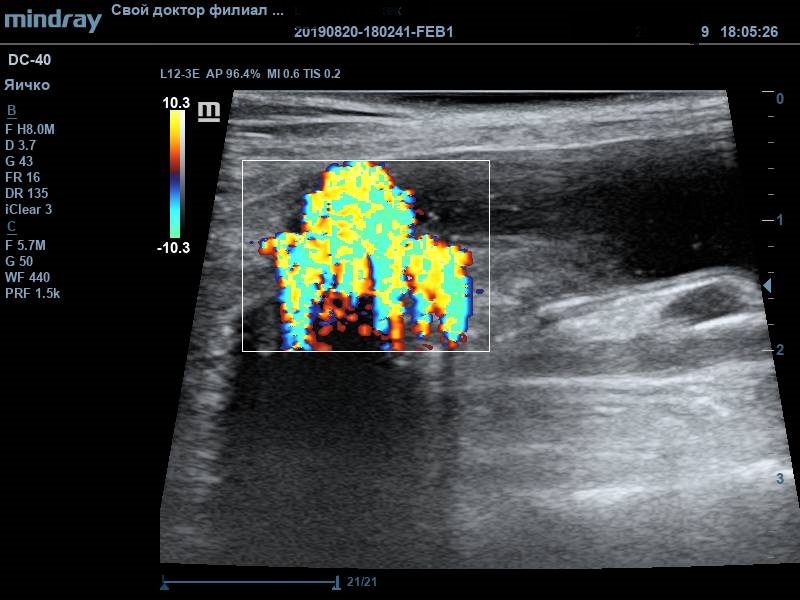

Во время УЗ-диагностики были обнаружены следующие изменения: неравномерное утолщение стенки мочевого пузыря (от 0,3 до 0,7см), слизистый слой гиперэхогенный. В содержимом мочевого пузыря присутствовал обильный крупнодисперсный осадок. В области мочевого треугольника визуализировалось пристеночное рыхлое ассиметричное образование с признаками васкуляризации, размер образования 1,27*0,75см. По заключению данного исследования дифференциальным диагнозом стало новообразование мочевого пузыря, в т.ч. злокачественное. Подобный диагноз окончательно ставится только по результату гистологического исследования материала. Получение материла для проведения анализа возможно в подобных ситуациях только посредством травматической катетеризации или открытой биопсией. Если подтверждается наличие злокачественной опухоли, то в таком случае разрабатываются план хирургического лечения (если оно возможно) и схема курсов химиотерапии.